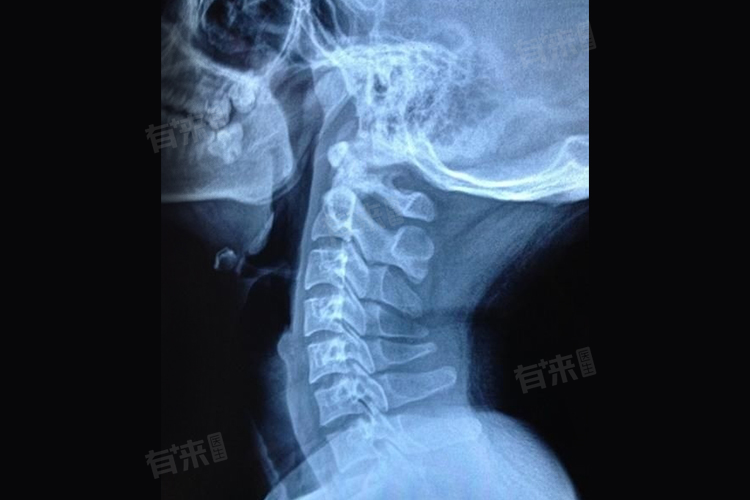

颈椎韧带钙化本身并不一定会直接导致瘫痪,但在特定情况下,可能增加瘫痪风险。颈椎韧带钙化是指颈椎周围的韧带,如前纵韧带、后纵韧带、黄韧带等,因长期劳损、退变、损伤等原因,发生钙盐沉积,导致韧带变硬、弹性降低。

- 重度钙化则较为严重,大量钙盐沉积使韧带显著增厚、变硬,严重压迫脊髓。此时患者除了上述症状加重外,还可能出现行走不稳、大小便功能障碍等脊髓受压症状,若不及时干预,随着病情进展,瘫痪风险会逐渐升高。

当颈椎韧带钙化压迫脊髓时,会干扰脊髓的正常生理功能。脊髓是人体重要的神经传导通路,负责传递大脑与身体各部位之间的神经信号。钙化的韧带压迫脊髓,会导致脊髓局部血液循环障碍,神经细胞因缺血缺氧而受损,神经传导功能受到影响。随着压迫时间延长和程度加重,神经细胞损伤逐渐加剧,可导致肢体感觉减退、肌肉力量下降。若压迫持续得不到解除,脊髓功能严重受损,最终可能导致患者肢体完全失去运动和感觉功能,造成瘫痪。